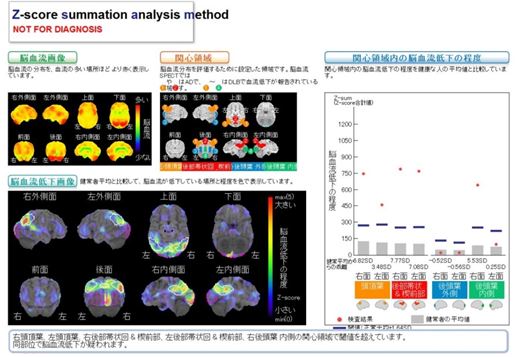

Fabry病│医學事始 いがくことはじめ, 核医学(RI検査)(医療関係者の方向け) | 京都市立病院,

核医学(RI検査)(医療関係者の方向け) | 京都市立病院, 第52回日本核医学会学術総会/第32回日本核医学技術学会総会学術,

第52回日本核医学会学術総会/第32回日本核医学技術学会総会学術, 第52回日本核医学会学術総会/第32回日本核医学技術学会総会学術,